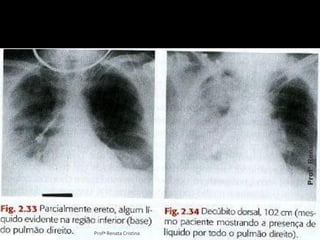

A. traqueia -ar B. ápice do pulmão C. Carina D. A base do pulmão E. diafragma F. ângulo costofrênico G. hilo Profª Renata Cristina ProfªRenataCristina